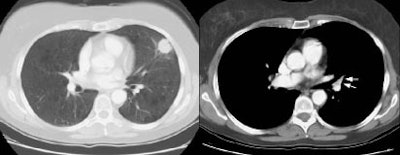

Example 2: False-negative CT exam -- this patient had an adenocarcinoma in the right upper lobe that measured less than 3 cm in size (T1 lesion). The ipsilateral mediastinal nodes identified by staging CT were not pathologic by size criteria. The surgical team elected to proceed to thoracotomy without mediastinoscopy. At surgery, the small right paratracheal nodes which measured less than 1 cm where found to contain microscopic foci of tumor (N2 nodes). The patient was staged histopathologically as T1N2M0 (Stage IIIA).